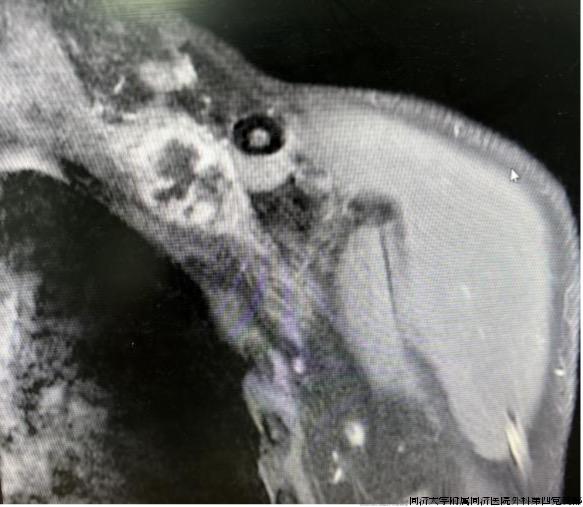

54岁的老陈近期出现左肩部疼痛、上肢麻木,自己一直以颈椎病来治疗,但症状并未缓解且逐步加重,当地医院行B超检查提示左肩部深处有一可疑肿块。由于该处血管神经丛密布,手术风险极大。为进一步治疗老陈来到同济医院骨科就诊,樊健教授详细的体格检查后发现他的左侧锁骨上内缘深处可扪及一实性肿块,叩击后左上肢疼痛麻木加重,结合既往病史考虑为臂丛神经锁骨内段的神经肿瘤。入院后的MRI、肌电图等证实为做锁骨内臂丛神经占位病变(图1)。

图1锁骨内段臂丛神经占位